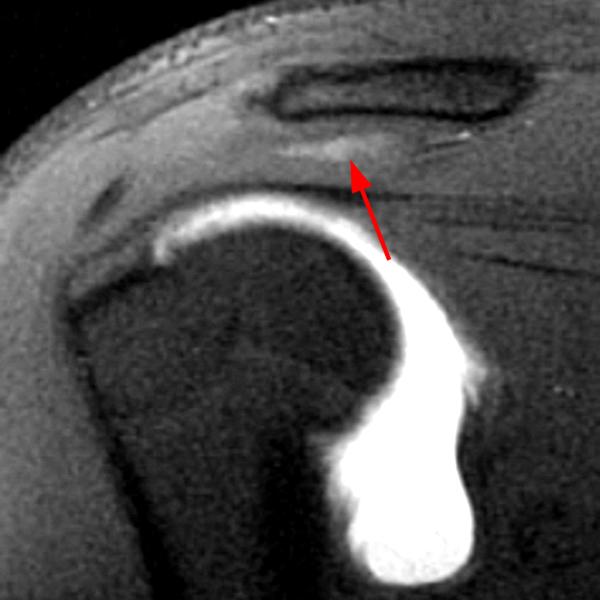

Shoulder Cysts Mri

From radsource.us

Shoulder Cysts Radsource Back Shoulder Cyst It's important to pay attention to the lump on your shoulder and its associated symptoms to determine if you should seek medical attention. Lumps on the shoulder are often associated with traumatic events, however, causes can also be inflammatory, cancerous, or environmental. They can develop anywhere around the shoulder but are the most common type of cyst on back of. Back Shoulder Cyst.